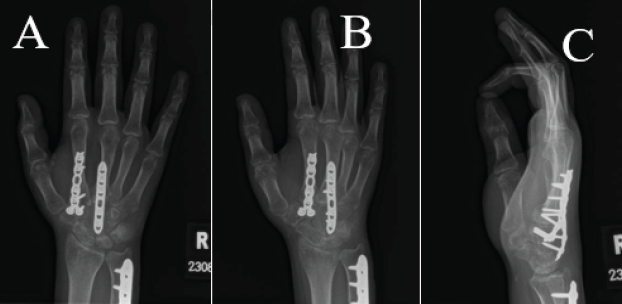

Two weeks postoperatively, the patient’s numbness was improving; she was transitioned to a removable orthosis and was started in hand therapy (Fig. 3). Six weeks postoperatively, the patient was allowed to begin light use and aggressive passive range of motion. At 12 weeks postoperatively, radiographs demonstrated healing of the fractures and no recurrent dislocations (Fig. 4). The patient had no complaints of pain and was using her hand for activities of daily living. There was significant stiffness in the metacarpophalangeal (MCP) joints (index finger 0–25°, middle finger, ring finger, and small finger 0–45°) but a full range of motion in the interphalangeal joints. The patient was offered removal of hardware at this time, but elected to wait 2 months until her winter break. At 4 months postoperatively, the patient’s DASH score had improved from 83.33 preoperatively to 11.67 postoperatively.

Figure 3: Two-week post-operative radiographs of the right hand in a volar splint. (a) Posteroanterior view, (b) lateral view, and (c) oblique view. X-rays show bridge plating of the second and third carpometacarpal base fracture dislocations with stabilization of the capitate fracture through the construct and fixation of ulna shaft fracture.

Figure 4: Three-month post-operative radiographs of the right hand. (a) Posteroanterior view, (b) oblique view, and (c) lateral view. X-rays show bridge plating of the second and third carpometacarpal base fracture dislocations and fixation of ulna shaft fracture.